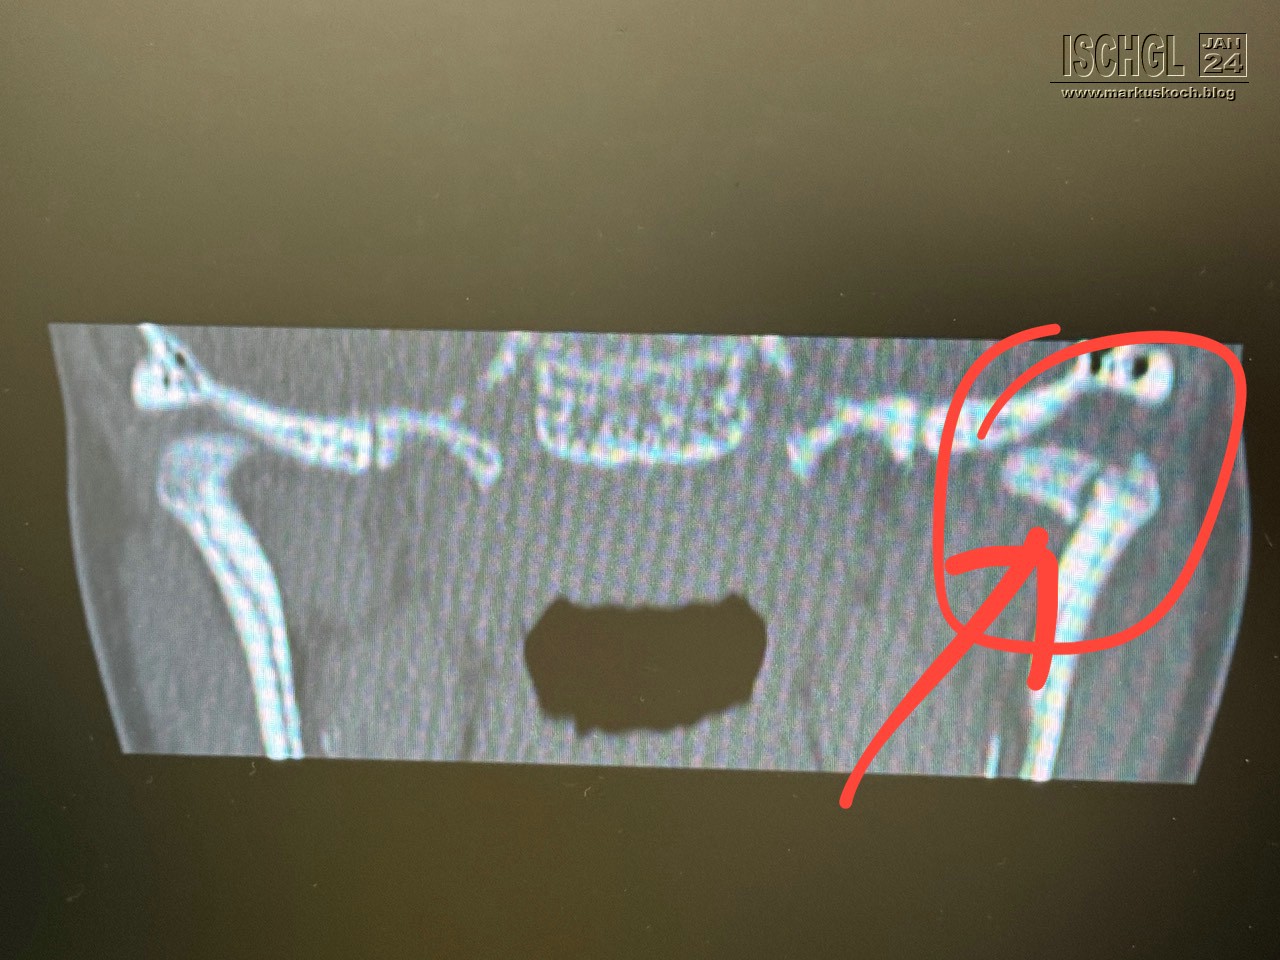

Leider ist Luca auf der Eislauffläche bzw. am nicht präparierten Rand beim Bremsen aufs Kinn gefallen. Anschließend Arzt in Ischgl und weil er nicht so exakt am Kopf röntgen konnte, sollten wir nach Zams ins Krankenhaus. Dort wurde dann genau nachgeschaut und sogar ein CT gemacht. Leider hat sich herausgestellt, dass er sich das Gelenkköpfchen des Unterkiefers gebrochen hat.